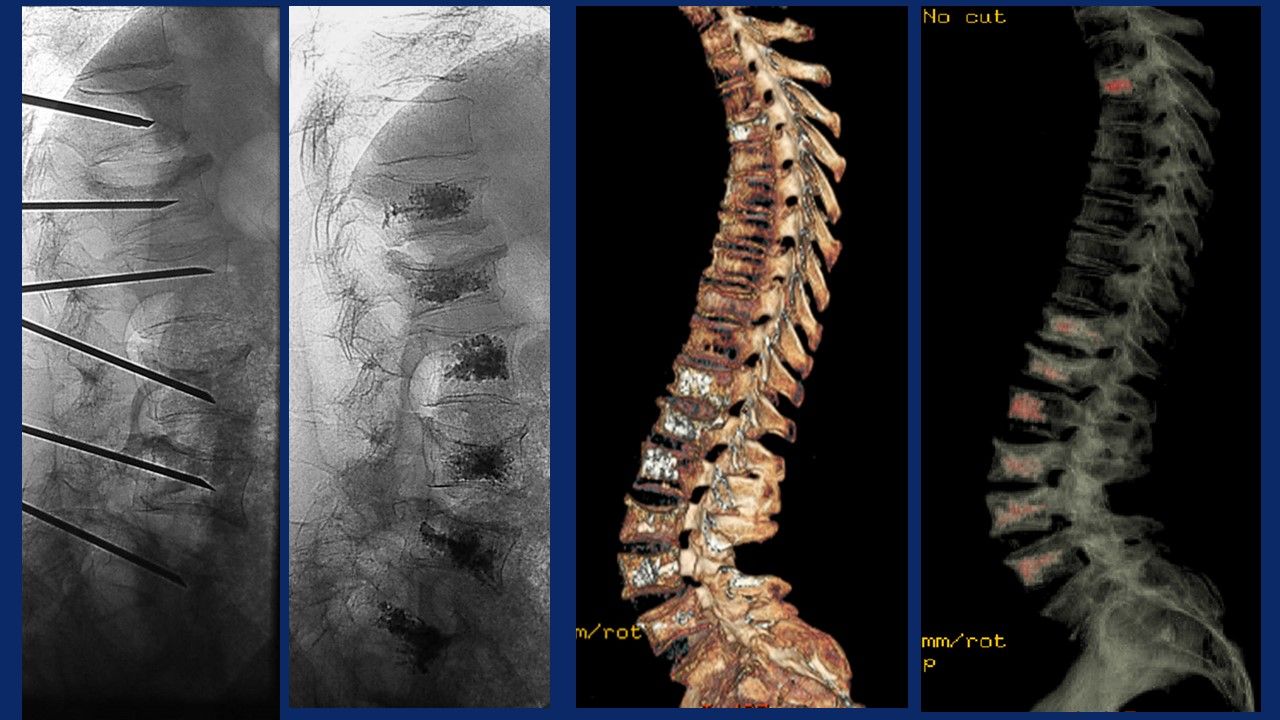

Ho maturato una notevole esperienza nella chirurgia mininvasiva percutanea del rachide, in particolar modo:

- nel trattamento della patologia discale mediante procedure di discectomia percutanea sotto guida fluoroscopica:

Nucleoplastica, Discectomia meccanica, Discectomia mediante laser, Discectomia Endoscopica, Discectomia mediante Discogel

- nel trattamento delle fratture vertebrali, su base osteoporotica o neoplastica mediante Vertebroplastica, Chifoplastica, Osteoplastica, Termoablazione o Crioablazione con Osteoplastica

- nel trattamento delle instabilità del rachide (spondilolistesi congenite o degenerative) mediante interventi di stabilizzazione mininvasiva percutanea con barre e viti , barre e viti cementate, tlif, plif, xlif, artrodesi delle faccette articolari.